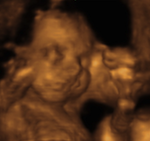

Vorsorge-Ultraschall

In der Schwangerenvorsorge sind drei Ultraschalluntersuchungen vorgesehen:

• 09. - 12. SSW: Messen der Länge und positiver Herzaktion und Festlegen des Geburtstermines.

• 19. - 22. SSW: Feststellung von Größe, Gewicht, Fruchtwassermenge und Plazentasitz

• 29. - 32. SSW: Feststellung von Größe, Gewicht, Fruchtwassermenge und Plazentasitz.